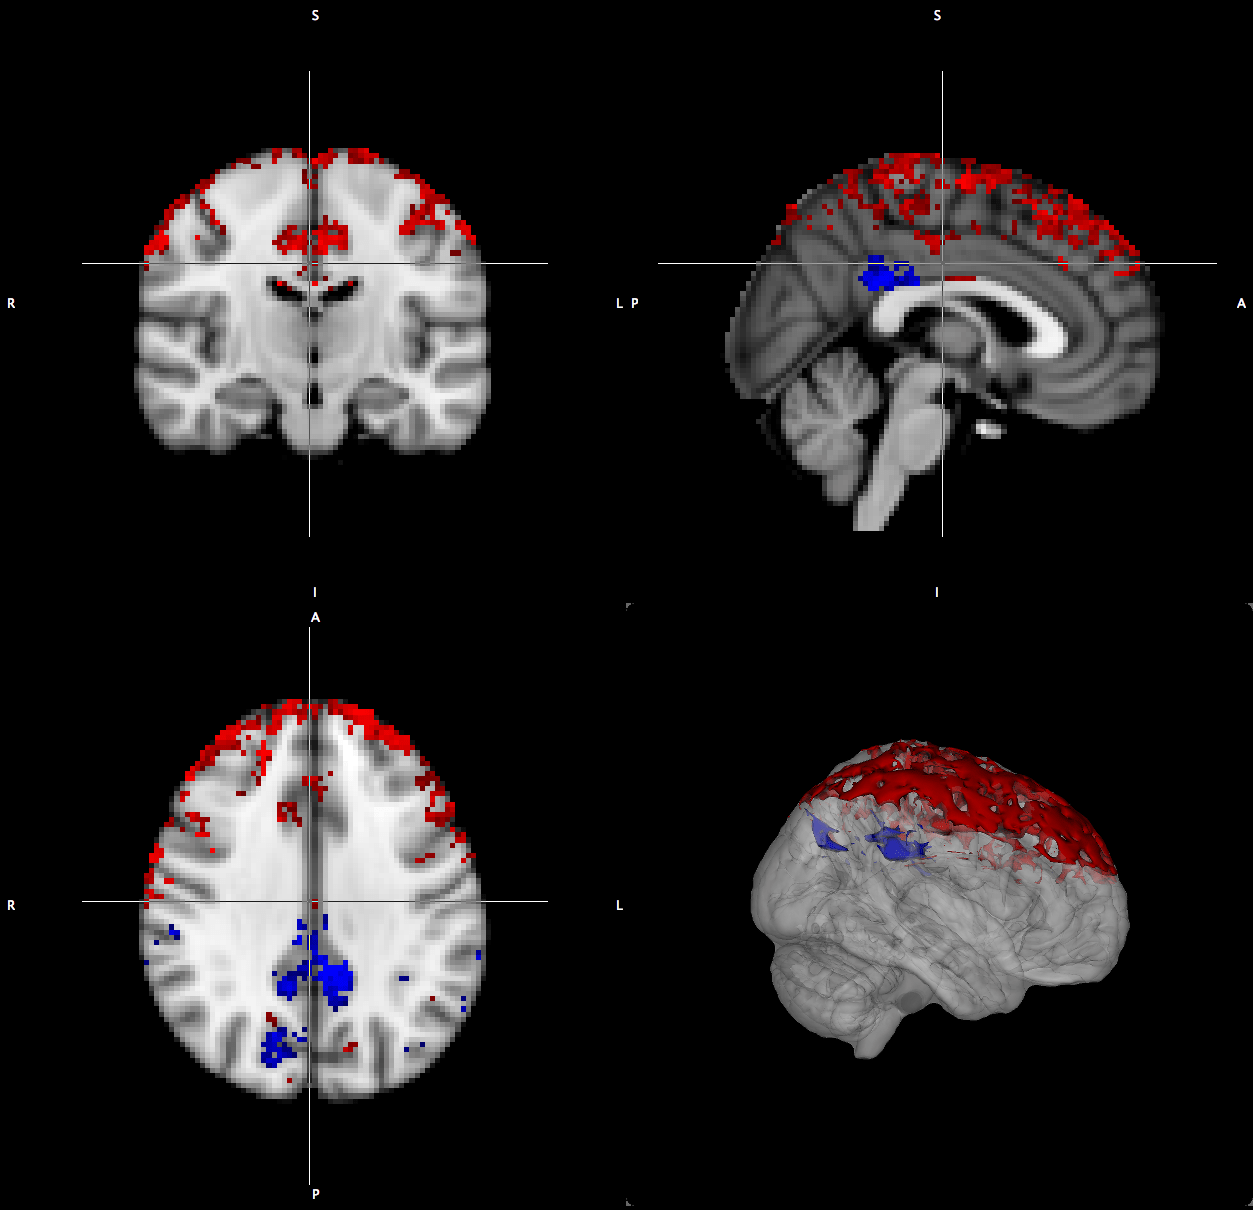

- Investigating the acute physiologic affects of hypoxia on cerebrovascular, neurochemical and metabolic function in the brain. These studies involve:

- utilizing arterial spin labeling to measure cerebral blood flow

- BOLD imaging to measure changes to neurovascualr coupling,

- Proton MRS investigations of excitatory and inhibitory neurometabolites

- functional MRS to probe neural activity independent of vascular complications